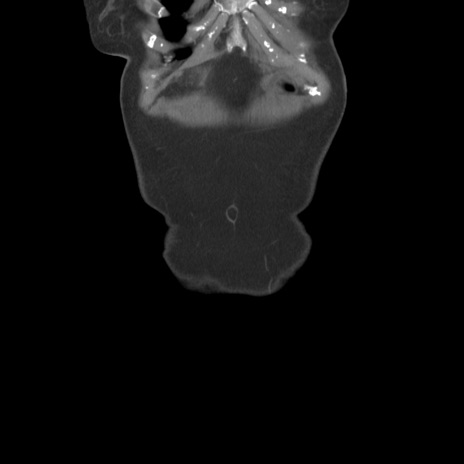

症例19(冠状断像)

【症例】80歳代女性

【主訴】下腹部痛

【現病歴】約8時間前より下腹部痛の出現あり、救急外来受診。

【既往歴】両側付属器切除

【身体所見】意識清明、下腹部正中に手術痕あり、その部位に一致して圧痛と反跳痛あり。腸蠕動音は亢進。

【データ】WBC 9300、CRP 0.15